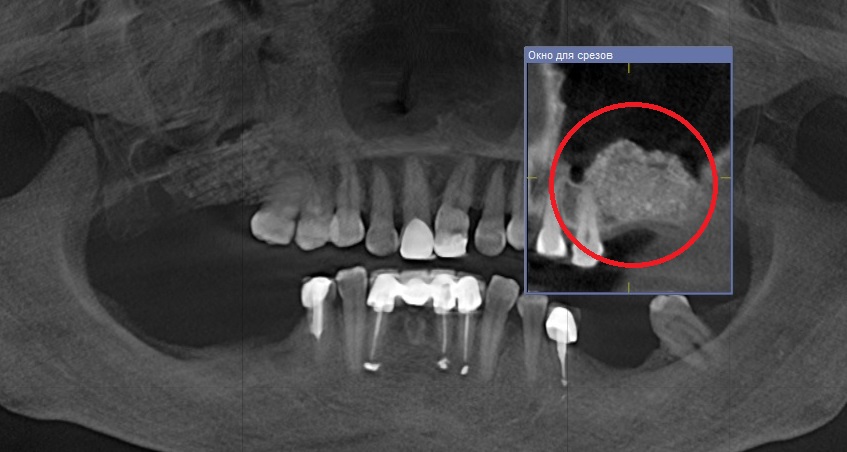

Рентгеновские снимки посттравматического остеомиелита челюсти: Медицинские случаи

Раздел: Образы вокруг